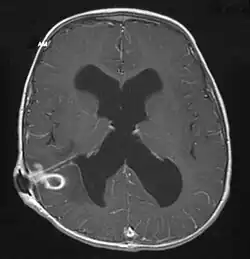

The diagnosis is established by a computed tomography (CT) (with contrast) examination. At the initial phase of the inflammation (which is referred to as cerebritis), the immature lesion does not have a capsule and it may be difficult to distinguish it from other space-occupying lesions or infarcts of the brain. Within 4–5 days the inflammation and the concomitant dead brain tissue are surrounded with a capsule, which gives the lesion the famous ring-enhancing lesion appearance on CT examination with contrast (since intravenously applied contrast material can not pass through the capsule, it is collected around the lesion and looks as a ring surrounding the relatively dark lesion). Lumbar puncture procedure, which is performed in many infectious disorders of the central nervous system is contraindicated in this condition (as it is in all space-occupying lesions of the brain) because removing a certain portion of the cerebrospinal fluid may alter the concrete intracranial pressure balances and causes the brain tissue to move across structures within the skull (brain herniation).[14]

Ring enhancement may also be observed in cerebral hemorrhages (bleeding) and some brain tumors. However, in the presence of the rapidly progressive course with fever, focal neurologic findings (hemiparesis, aphasia etc.) and signs of increased intracranial pressure, the most likely diagnosis should be the brain abscess.[15]